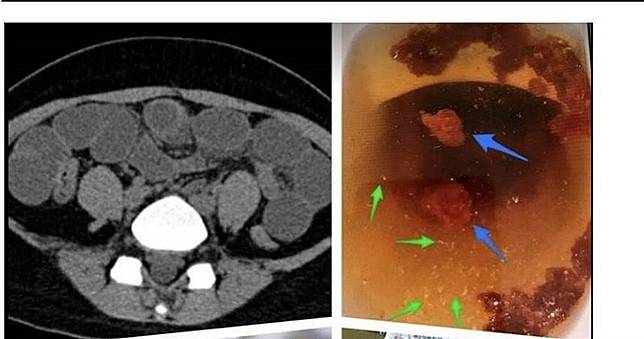

腸阻塞。(圖/報系資料照/李宏昌提供)

後來少女開始出現腹痛、嘔吐症狀,不時還會吐出黃綠色汁液,被家人緊急送醫。李宏昌指出,進行超音波時發現腸阻塞,後續透過腹腔鏡手術取出一團團棉絮異物;後來少女家屬在整理住院衣物時,發現衣物上有破損,追問之下才知道少女吃棉花。